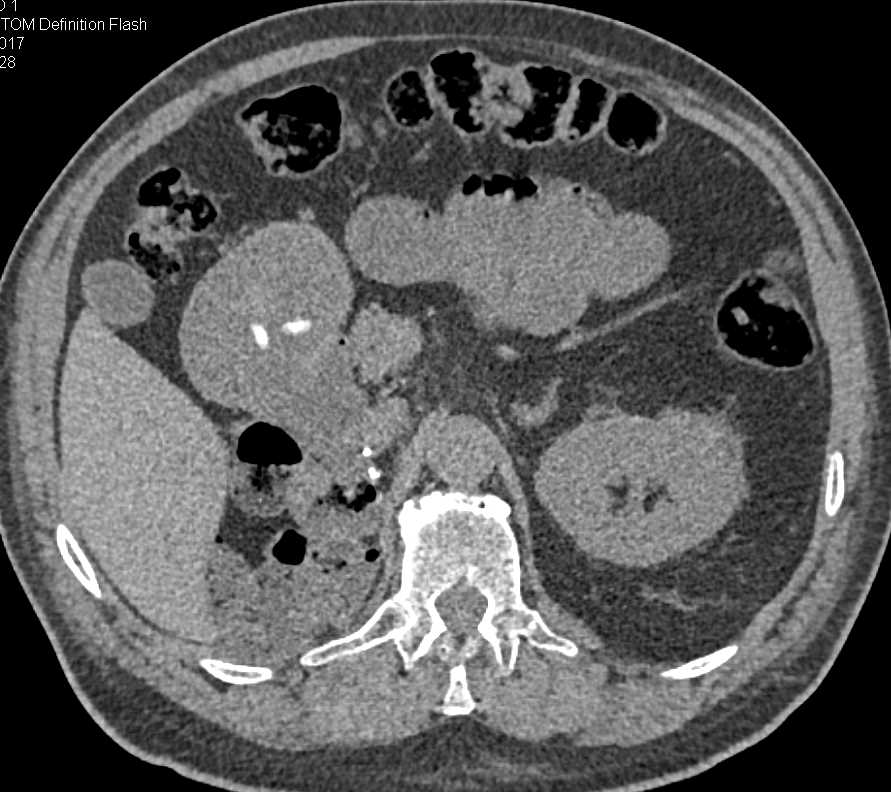

Gastric Adenocarcinoma in the Body of the Stomach